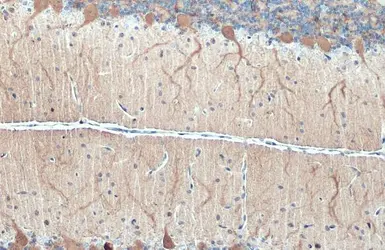

Anti-DARPP-32 antibody used in IHC (Paraffin sections) (IHC-P). GTX133350

GTX133350 IHC-P Image

DARPP-32 antibody detects DARPP-32 protein at cytoplasm by immunohistochemical analysis.

Sample: Paraffin-embedded rat cerebellum.

DARPP-32 stained by DARPP-32 antibody (GTX133350) diluted at 1:500.

Antigen Retrieval: Citrate buffer, pH 6.0, 15 min